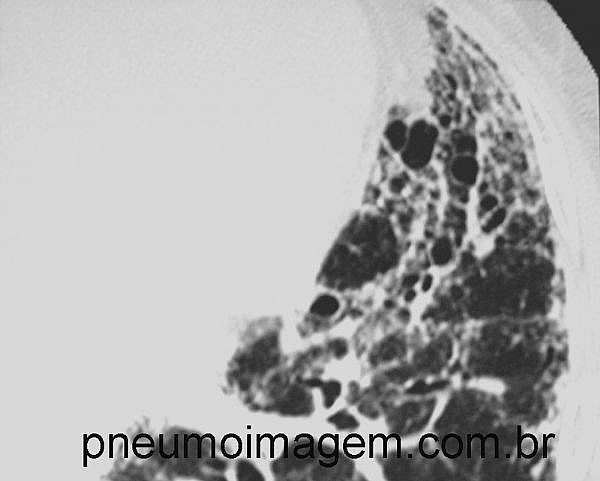

APROVADA NOVA DROGA NO BRASIL PARA O TRATAMENTO DA FIBROSE PULMONAR IDIOPÁTICA

Foi aprovada no Brasil nova droga para o tratamento da Fibrose Pulmonar Idiopática nessa segunda-feira, dia 26/10. O Nintedanibe, cujo nome comercial será OFEV, é produzido pela Boehringer-Ingelheim.